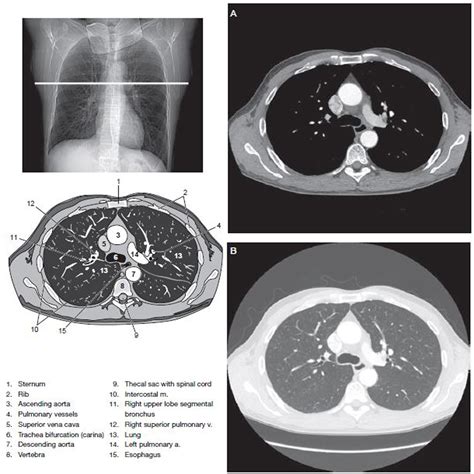

A CT of thorax, or computed tomography scan of the chest, uses X-rays and computer technology to create cross-sectional images of the thoracic cavity. These images provide a detailed view of the lungs, heart, blood vessels, and other structures within the chest. The procedure is particularly useful for diagnosing conditions such as lung cancer, pneumonia, and heart disease.

Interpreting the results of a CT of thorax involves a radiologist reviewing the images to identify any abnormalities. The findings are then communicated to the referring physician, who will discuss them with the patient. Common conditions that can be detected include:

Radiologists use advanced software to analyze the images, providing detailed reports that guide further treatment and management.

• ct of thorax anatomy